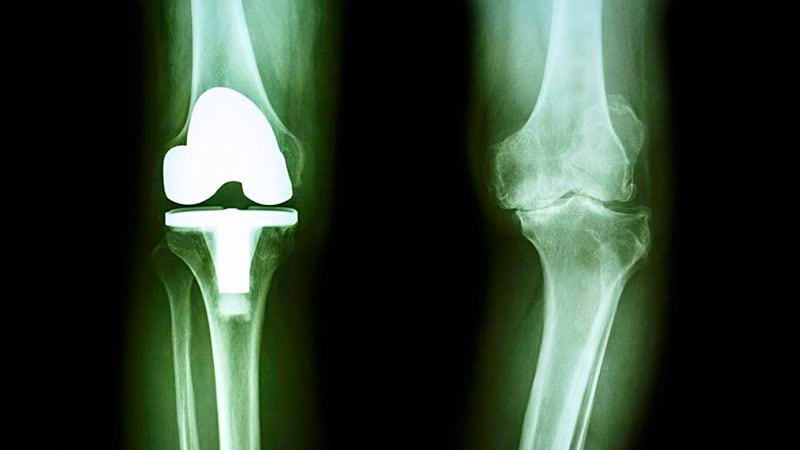

Arthroplasty

Knee Surgery Surge Not Linked to Premature Intervention -

All in Stride: Few Age Limitations for Joint Replacement -

Prosthetic Knee Infection by a-hemolytic Streptococcus Species